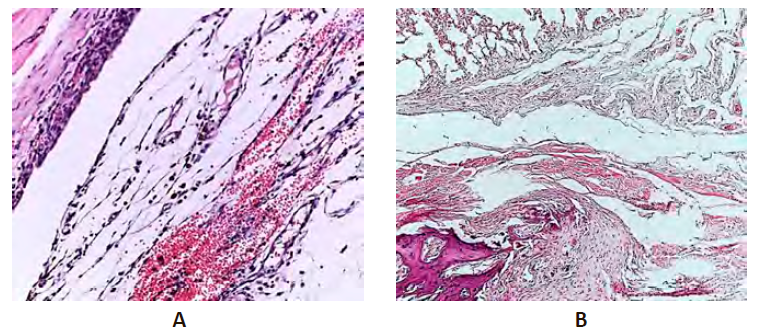

Рисунок 5 – Экспериментальная травма грудной клетки 10-е сутки

Примечание: А. Группа НКт. Б. Группа PRPт. Окраска гематоксилином и эозином. Ув. ×400.

Объем серозно-геморрагического экссудата на 20-е сутки эксперимента в группе НКт был незначителен, выявлен отек соединительной ткани, представленной хаотично локализованными волокнами, по типу миксоматозной трансформации. Определялись единичные сосуды и диффузная преимущественно нейтрофильная воспалительная инфильтрация. Отмечалось несоответствие незрелых плевральных сращений сроку эксперимента (рис. 6А).

При введении PRP на 20-е сутки определялись молодые плевральные сращения, содержащие в своем составе волокна, ориентированные параллельно поверхности стенок плевральной полости. В рыхло расположенных волокнах соединительной ткани визуализировались единичные гранулы гемосидерина, что связано с изменением проницаемости эндотелия и базальной мембраны и свидетельствовало о продолжающемся адгезиогенезе (рис. 6Б).

Рисунок 6 – Экспериментальная травма грудной клетки 20-е сутки

Примечание: А. Группа НКт. Окраска гематоксилином и эозином. Ув. ×100. Б. Опытная группа PRPт. Окраска гематоксилином и эозином. Ув. ×200.

В группе НКт на 30-е сутки эксперимента спайки по-прежнему были незрелыми. Кровенаполнение сосудов и присутствие гранул гемосидерина с сидерофагами свидетельствовало о продолжающемся ангиогенезе и формировании плевральных сращений. Сосуды были тонкостенными, полнокровными и располагались неравномерно среди волокон соединительной ткани. Отмечалось наличие единичных лимфоцитов, плазмоцитов и нейтрофилов, а также обилие макрофагов (сидерофагов) (рис. 7А).

При гистологическом исследовании морфологических изменений в плевральной полости при биостимуляции адгезиогенеза введением плазмы, обогащенной тромбоцитами к окончанию эксперимента определялись зрелые сращения в области перелома ребер. Спайки сформированы строго ориентированными коллагеновыми волокнами и включали в свой состав фибробласты, фиброциты, с единичными в поле зрения сосудами (рис. 7Б).

Рисунок 7 – Экспериментальная травма грудной клетки 30-е сутки

Примечание: А. Группа НКт. Окраска гематоксилином и эозином. Ув. ×200. Б. Опытная группа PRPт. Окраска гематоксилином и эозином. Ув. ×400.